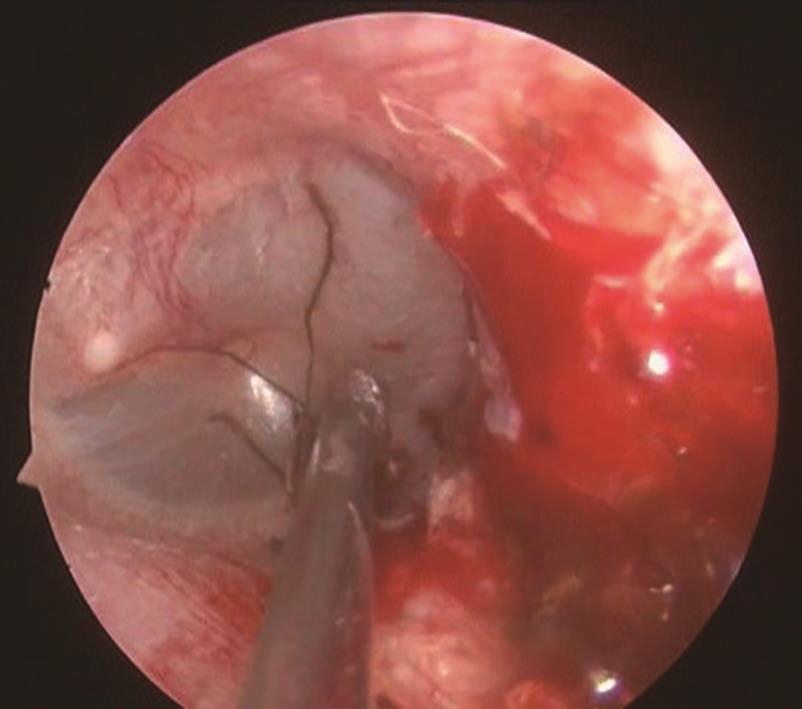

3.若外耳道内异物为活昆虫,可先滴入液体石蜡或丁卡因溶液等使昆虫固定、麻痹或死亡,然后用吸管、镊子或鳄鱼钳取出(图5-4)。

图5-4 麻痹或死亡昆虫可